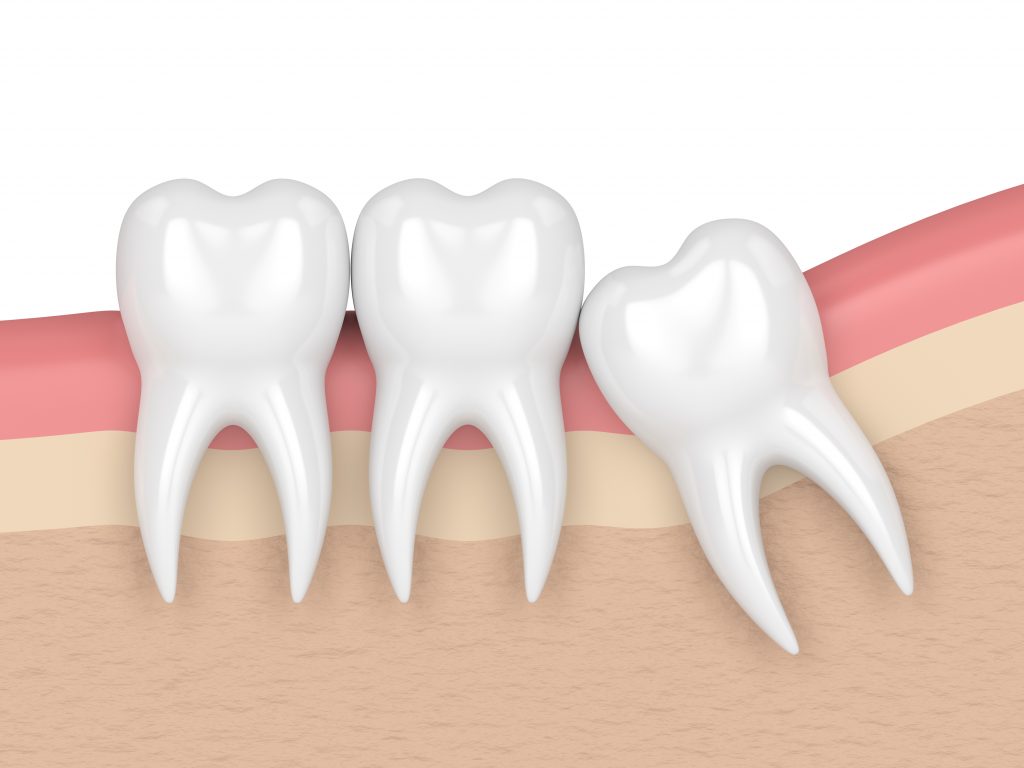

2. La falta de espacio

Al ser las últimas en aparecer, muchas veces el espacio en la mandíbula o el maxilar no es suficiente.

Tus terceros molares pueden presionar a los demás dientes, lo cual puede llegar a torcerlos y causar inflamación, dolor y molestias en tus encías.

3. Por la posición o dirección que traen

La tercera razón es la posición de las muelas de juicio.

Es posible que la posición durante su desarrollo no sea la ideal y tus cordales queden “encajadas” contra otros dientes. Esto les impide salir de manera correcta y las deja retenidas.

Te puede generar dolor de muelas, lesiones en los demás dientes y otros problemas dentales.